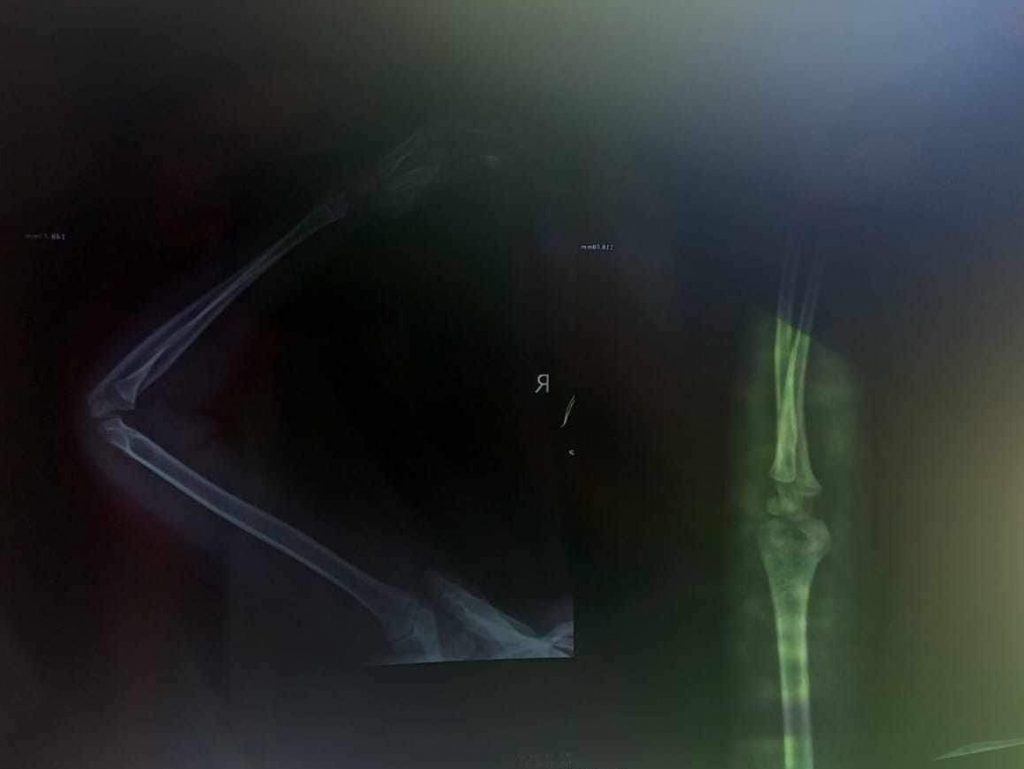

După o joacă în parc o copilă de 6 ani a fost adusă de părinți la secția Urgențe a Spitalului Municipal Brad. Deși i-a fost făcută o radiografie medicul de gardă nu și-a dat seama că micuța are mâna ruptă, motivând că este vorba doar despre o bătucire a osului și a mușchiului din zona respectivă. Chiar dacă fata acuza dureri groaznice, doctorița i-a prescris Voltaren.

Văzând că durerile fetiței persistă și mâna nu arăta foarte bine, părinții au hotărât să o ducă la o altă instituție medicală. Ajunși la Spitalul Județean din Deva, specialiștii au confirmat faptul că fata de 6 ani avea mâna ruptă. Aceștia au fost chemați la un alt control peste câteva zile.